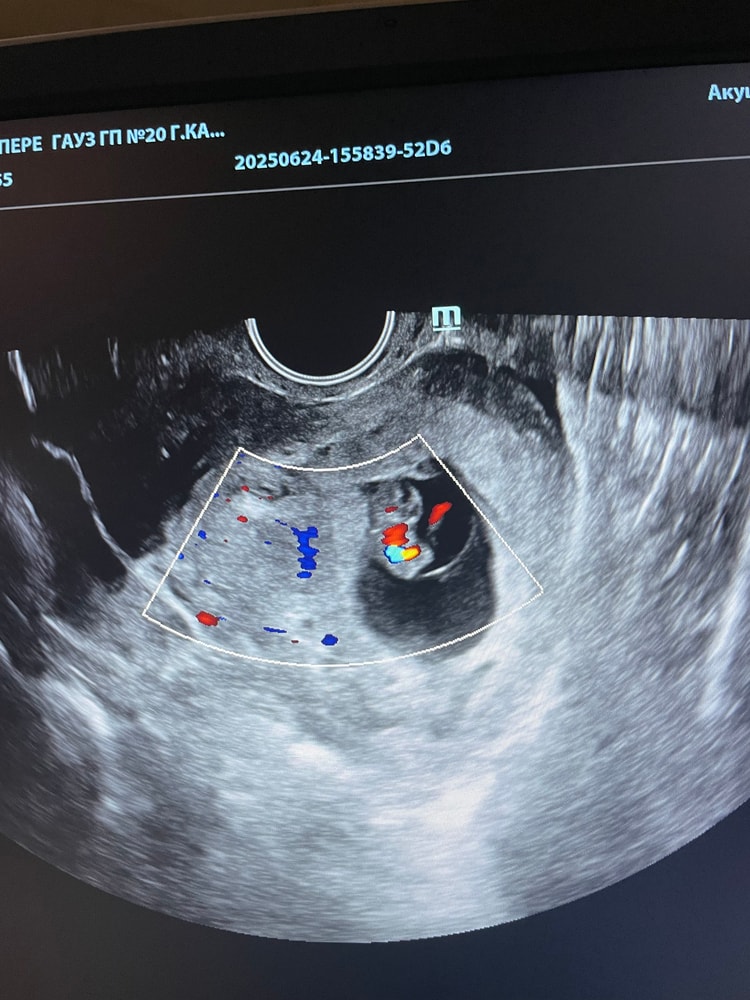

Больше вам скажу у меня не видели эмбрион при 6800 хгч, и даже 19000 😂 хотели почитстить,я писала отказ) и вот уже 8 недель,а у моего «пустого» пя чсс 178☺️ Изображение Но у меня в начале было подозрение на двойню,возможно поэтому хгч так рос Изображение